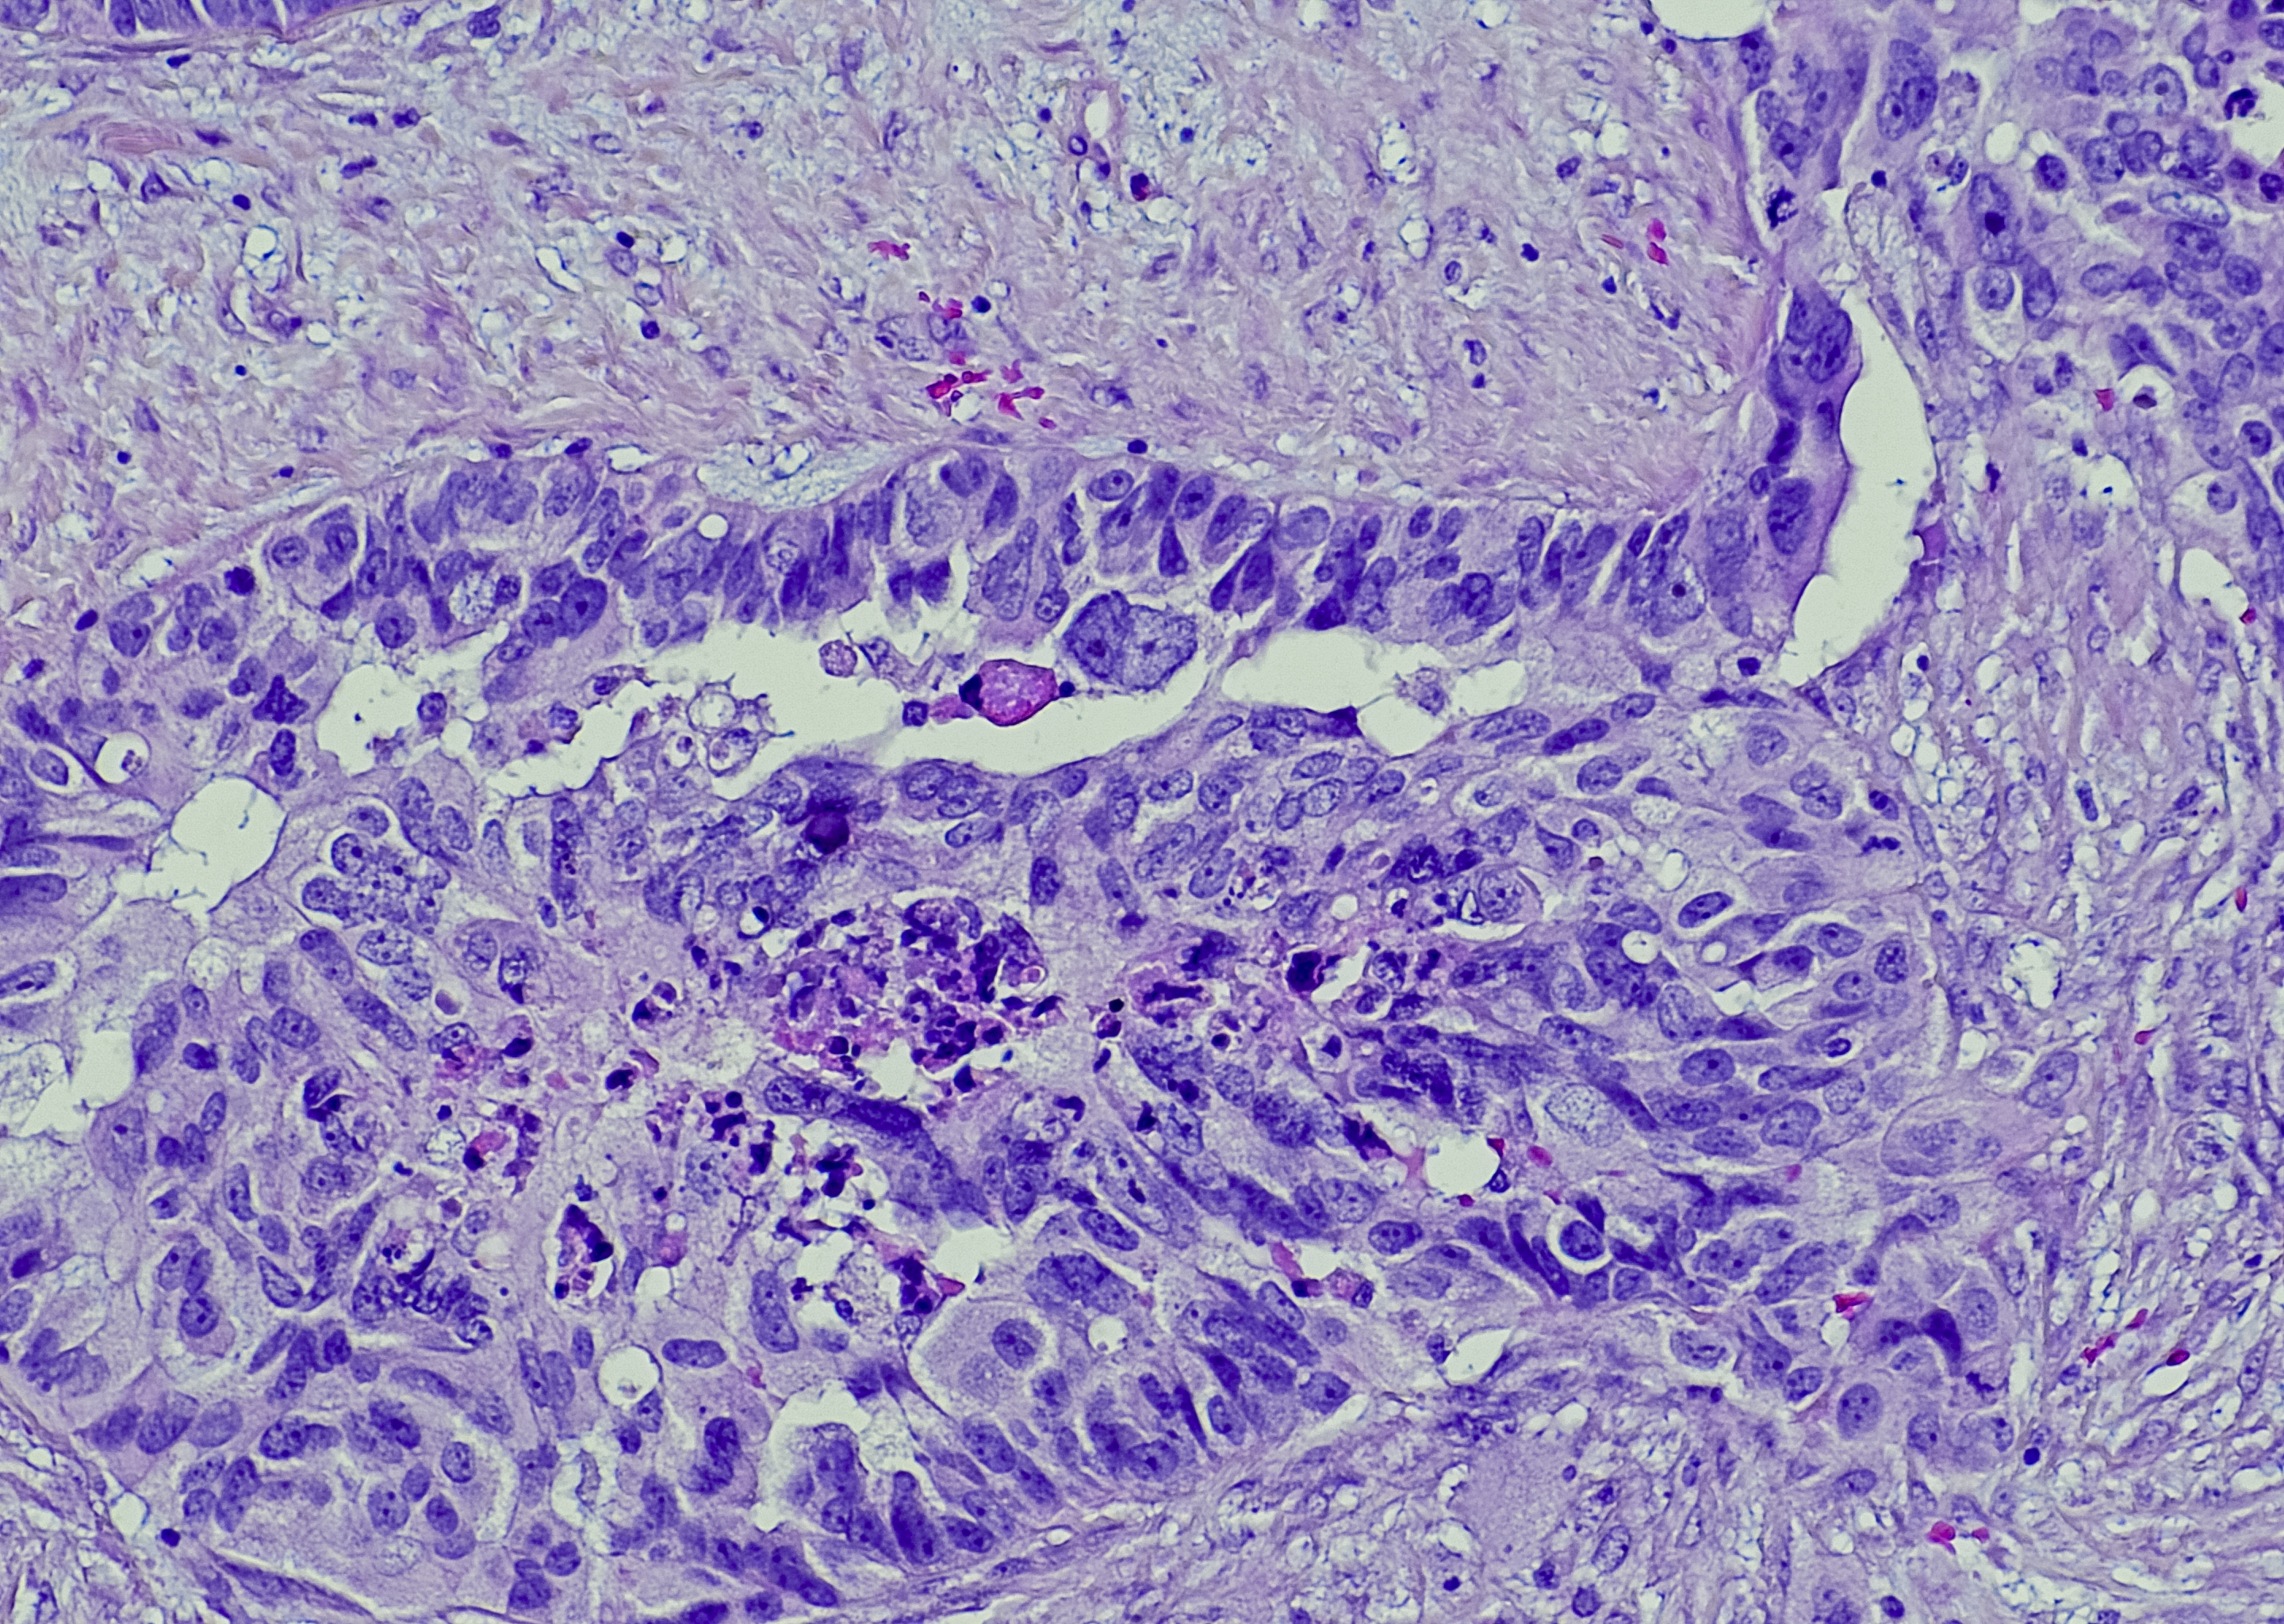

The ovaries are made up of germ cells, stromal cells and epithelial cells and each of these are susceptible to different cancers.

There are four main types of Ovarian Cancer, these are: